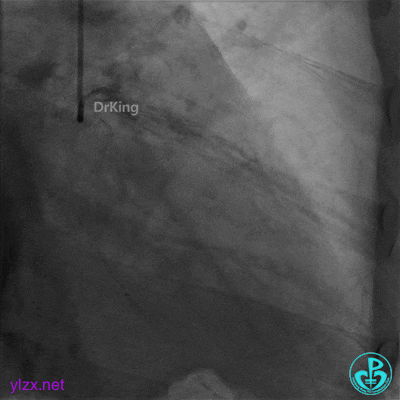

2.0×20mm球囊预扩张。

3.0×15mm双导丝球囊再次扩张。

双导丝球囊扩张后造影,血流缓慢,随即心率减慢至50次/分,血压降低至80/50mmHg,并出现短阵室速,随后意识丧失。